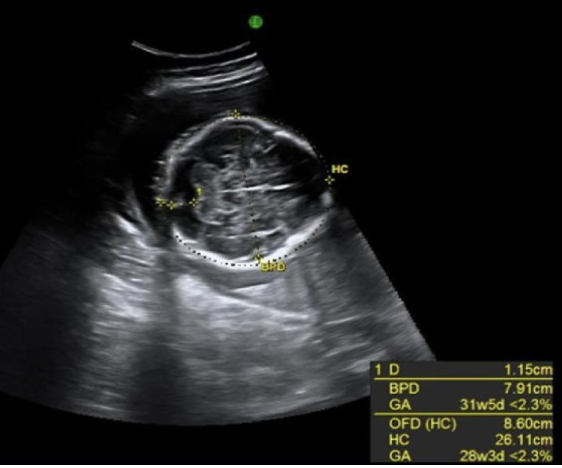

microcephaly is defined as HC measuring more than ___ standard deviations from the normal mean for the expected GA

a) 4

b) 2

c) 3

d) 1